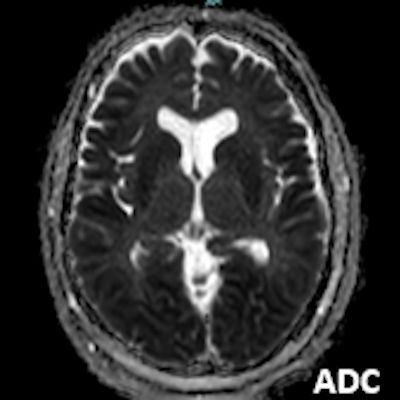

- A) Bilateral serebral kortekste (oklar) ve bazal ganglionlarda (oklar) yaygın DAG hiperintens, ADC hipointens difüzyon kısıtlamaları görülüyor.

- B) 9 gün sonraki difüzyon MR incelemede kortikal ve bazal ganglionlardaki difüzyon kısıtlamalarının gerilediği, bilateral serebral beyaz cevherde (oklar) ve internal kapsül arka bacağı- kortikospinal trakt boyunca (oklar) yaygın DAG hiperintens, ADC hipointens difüzyon kısıtlamalarının geliştiği izleniyor.

- T2A / FLAIR serilerde beyaz cevherde özellikle sentrum semiovalede diffüz yüksek sinyal görülür. Subkortikal U lifleri sıklıkla korunur.

- DAG görüntülemede sıklıkla belirgin difüzyon kısıtlaması görülür.